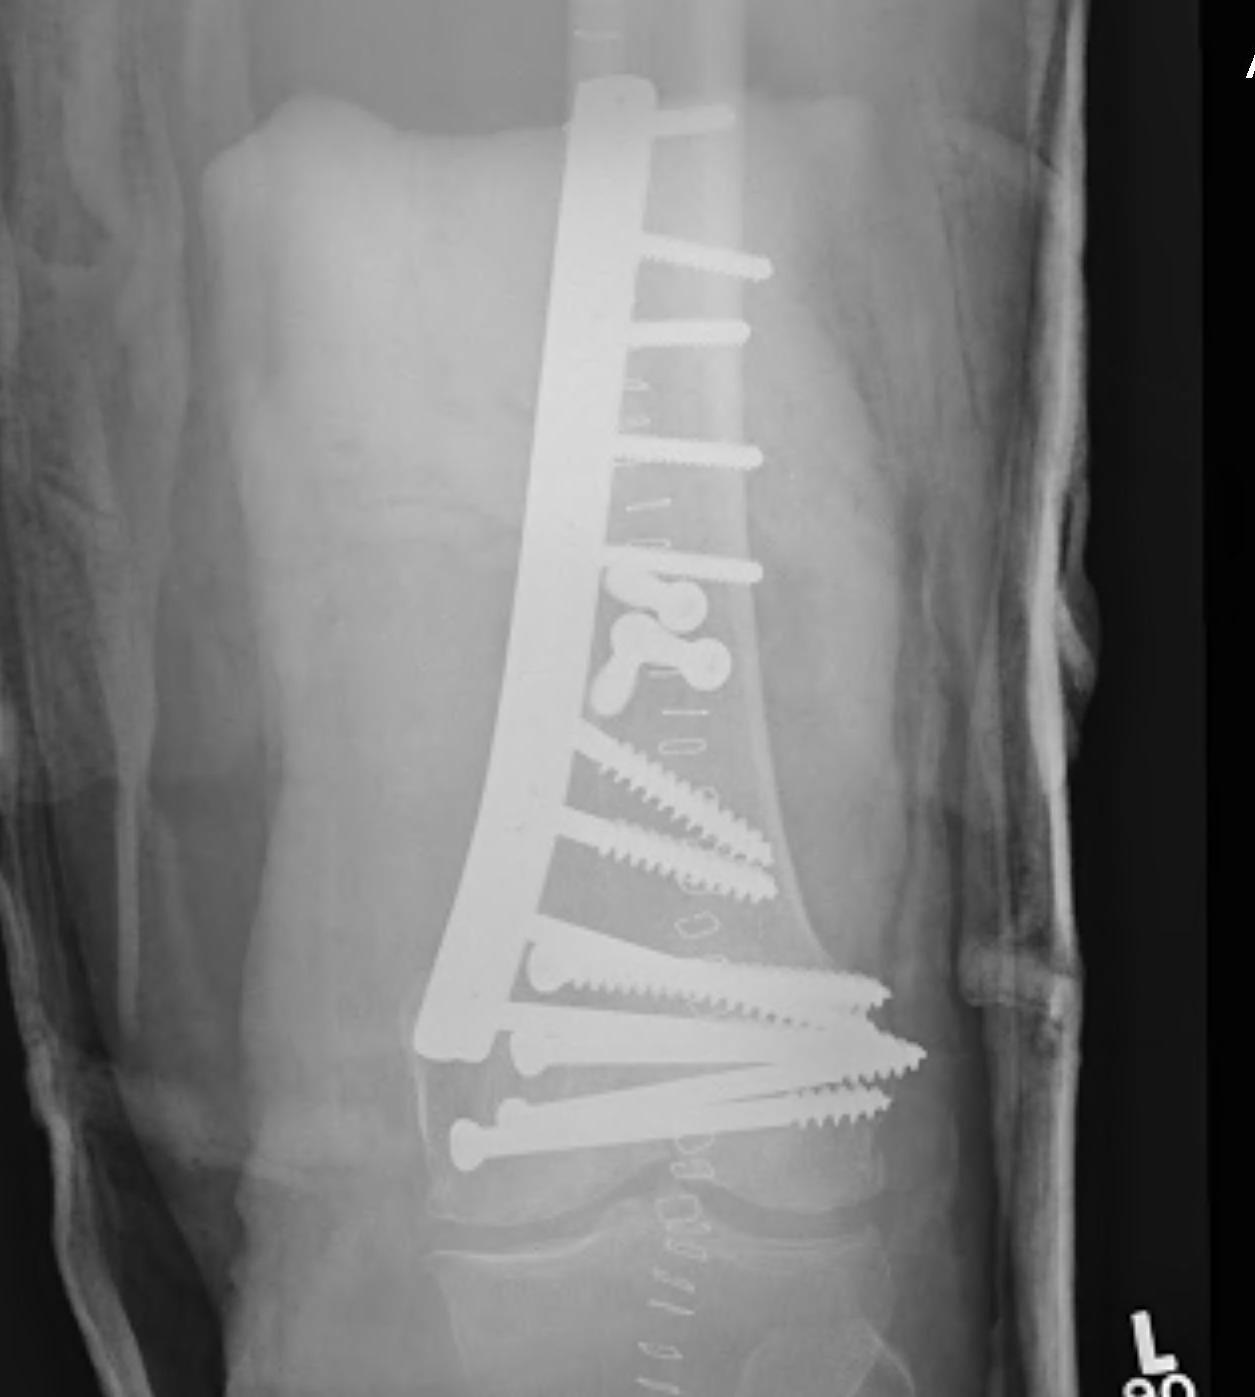

Bridging Plate

- used in the treatment of some multifragmentary fractures i.e. femur

- instead of individually fixing each fragment

- minimal disruption to blood supply

- reduction is performed indirectly

- compression is only sometimes possible

Concept

- 6 holes over each fragment if possible

- only fill 50% in intermediate fragments

- i.e. 3 bicortical screws sufficient

- near far near far concept